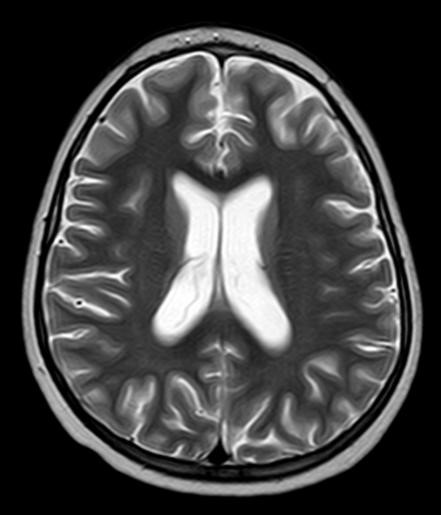

¿Cómo interpreta las imágenes de RM craneal?: